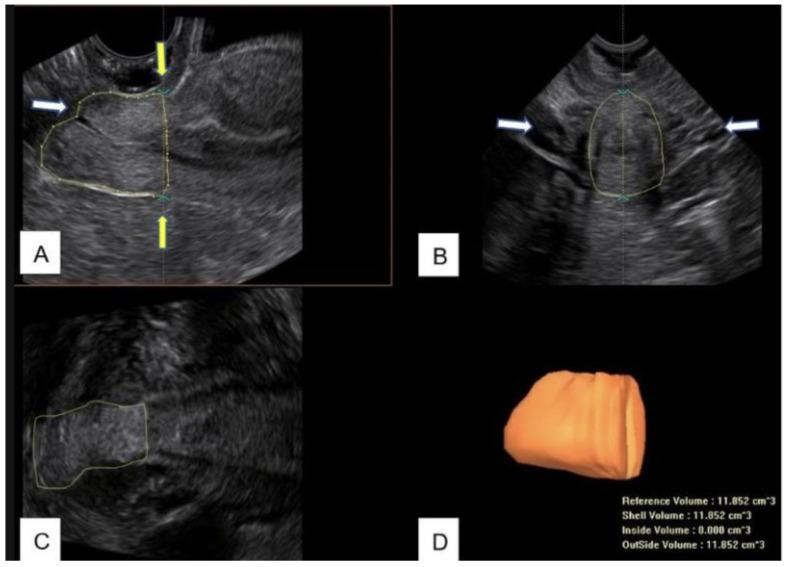

The objective of this research is to evaluate cervical regeneration after large loop excision of the transformation zone (LLETZ) through the identification of a new sonographic reference point at the level of the uterine margins. In the period March 2021-January 2022, a total of 42 patients affected by CIN 2-3 were treated with LLETZ at the University Hospital of Bari (Italy). Before performing LLETZ, cervical length and volume were measured with trans-vaginal 3D ultrasound. From the multiplanar images, the cervical volume was obtained using the Virtual Organ Computer-aided AnaLysis (VOCAL™) program with manual contour mode. The line that connects the points where the common trunk of the uterine arteries reaches the uterus splitting into the ascending major branch and the cervical branch was considered as the upper limit of the cervical canal. From the acquired 3D volume, the length and the volume of the cervix were measured between this line and the external uterine os. Immediately after LLETZ, the removed cone was measured using Vernier's caliper, and before fixation in formalin, the volume of the excised tissue was evaluated by the fluid displacement technique based on the Archimedes principle. The proportion of excised cervical volume was 25.50 ± 17.43%. The volume and the height of the excised cone were 1.61 ± 0.82 mL and 9.65 ± 2.49 mm corresponding to 14.74 ± 11.91% and 36.26 ± 15.49% of baseline values, respectively. The volume and length of the residual cervix were also assessed using 3D ultrasound up to the sixth month after excision. At 6 weeks, about 50% of cases reported an unchanged or lower cervical volume compared to the baseline pre-LLETZ values. The average percentage of volume regeneration in examined patients was equal to 9.77 ± 55.33%. In the same period, the cervical length regeneration rate was 69.41 ± 14.8%. Three months after LLETZ, a volume regeneration rate of 41.36 ± 28.31% was found. For the length, an average regeneration rate of 82.48 ± 15.25% was calculated. Finally, at 6 months, the percentage of regeneration of the excised volume was 90.99 ± 34.91%. The regrowth percentage of the cervical length was 91.07 ± 8.03%. The cervix measurement technique that we have proposed has the advantage of identifying an unequivocal reference point in 3D cervical measurement. Ultrasound 3D evaluation could be useful in the clinical practice to evaluate the cervical tissue deficit and express the "potential of cervical regeneration" as well as provide the surgeon useful information about the cervical length.

本研究的目的是通过在子宫边缘水平确定一个新的超声参考点,来评估转化区大环形切除术(LLETZ)后的宫颈再生情况。在2021年3月至2022年1月期间,意大利巴里大学医院对42例CIN 2 - 3患者进行了LLETZ治疗。在进行LLETZ之前,通过经阴道三维超声测量宫颈长度和体积。从多平面图像中,使用虚拟器官计算机辅助分析(VOCAL™)程序的手动轮廓模式获取宫颈体积。连接子宫动脉主干到达子宫并分为上行主要分支和宫颈分支的点的线被视为宫颈管的上限。从获取的三维体积中,测量这条线与子宫外口之间宫颈的长度和体积。LLETZ术后立即使用游标卡尺测量切除的锥体,并在固定于福尔马林之前,根据阿基米德原理通过流体置换技术评估切除组织的体积。切除的宫颈体积比例为25.50±17.43%。切除锥体的体积和高度分别为1.61±0.82 mL和9.65±2.49 mm,分别对应基线值的14.74±11.9